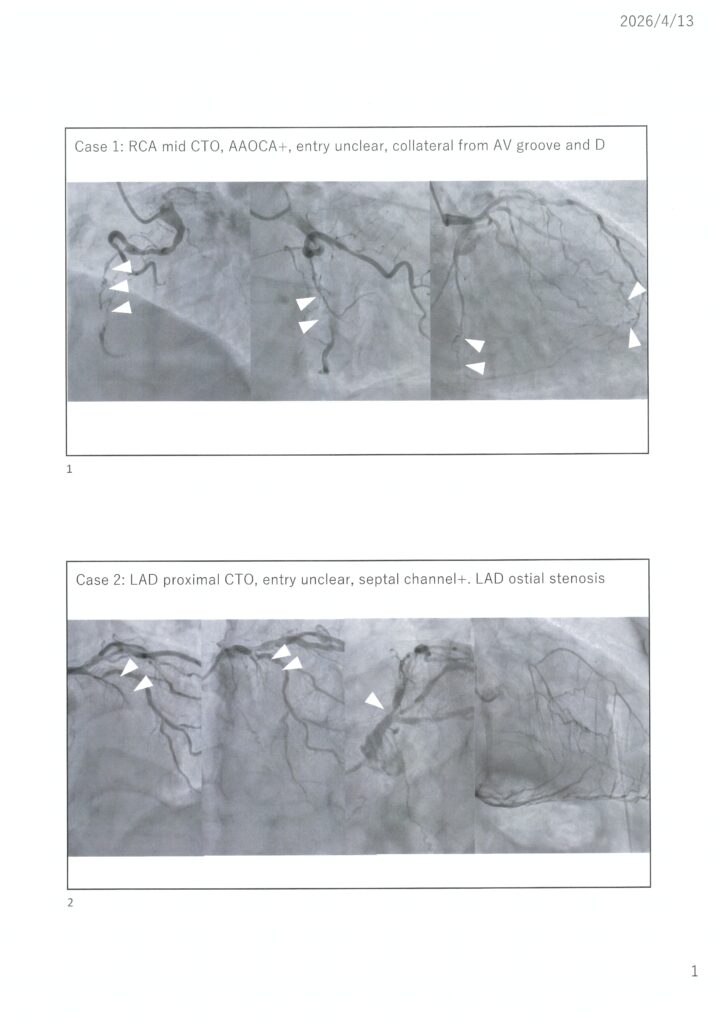

忖度のない我々のCTO治療から何かを学び取っていただければと思いますので、今年も奮ってご参加ください。Case1は伊藤、Case2は保坂Drで午前に治療予定です。Case3は小林、Case4は伊藤、Case5は堤、Case6は小林が午後治療予定です。可能な限り治療の全てをご覧いただけるようスイッチングなども考慮しつつ開催できればと思います。